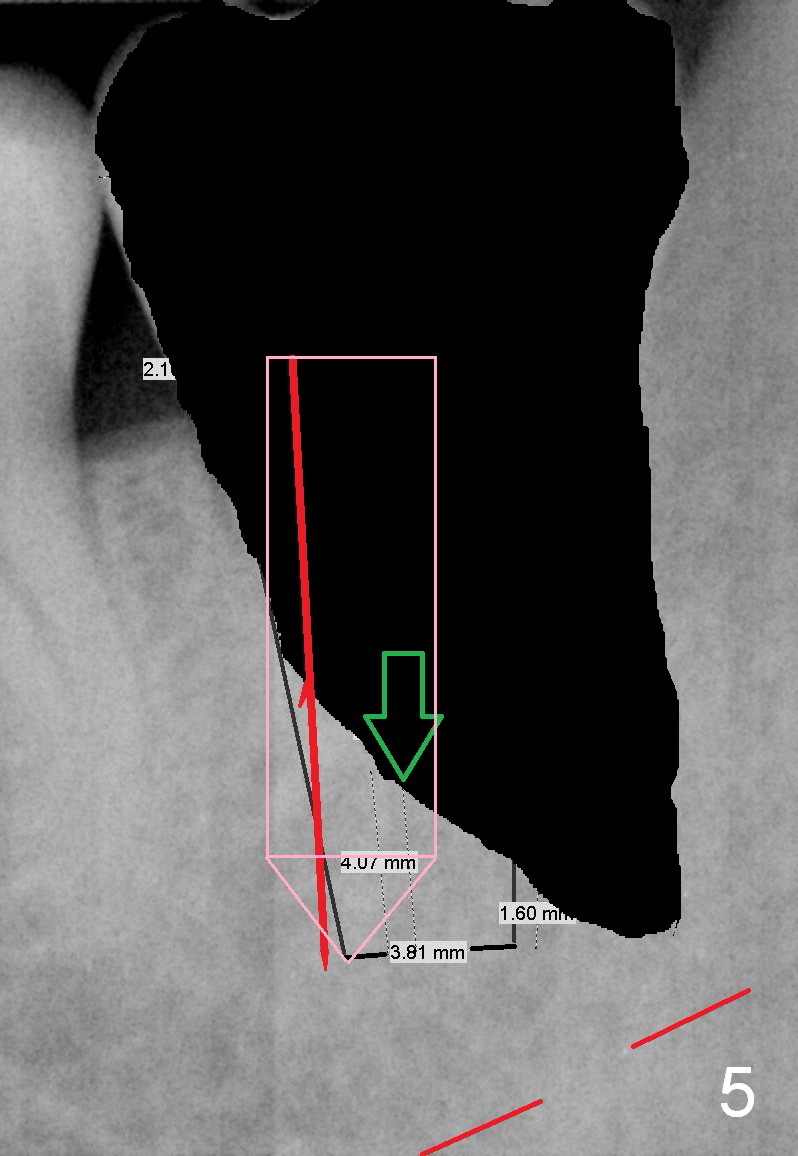

A 34-year-old man has distal deep caries of the lower 2nd molars. Root canal therapy turns out to be difficult on the right side due to bleach leakage. It would be also difficult to restore the distal defect. Finally he agrees to have extraction and implant. The result is good. He is ready to accept the same treatment for the left 2nd molar (Fig.1 (arrowheads: caries)). Metronidazole will be used for socket decontamination. Place a 5.9x10 mm bone-level implant 2 mm below the mesial crest (hopefully at the same level of the buccal crest) so that there is enough height to place an abutment (Fig.2). The apex of the implant is placed mesial to that of the root, since there is more bone, away from the superior border of the Inferior Alveolar Canal (red dashed line). The osteotomy is to be initiated in the middle of the mesial slope obliquely, more mesial (Fig.3 red line) than the center of the implant (green arrow). Once the lamina dura is penetrated, change the trajectory along the future long axis of the implant (Fig.4 red line). The depth will be 14 mm from the mesial gingival line (Fig.2). As the diameter of drills increases, the osteotomy tends to shift distal (Fig.5 pink arrow).